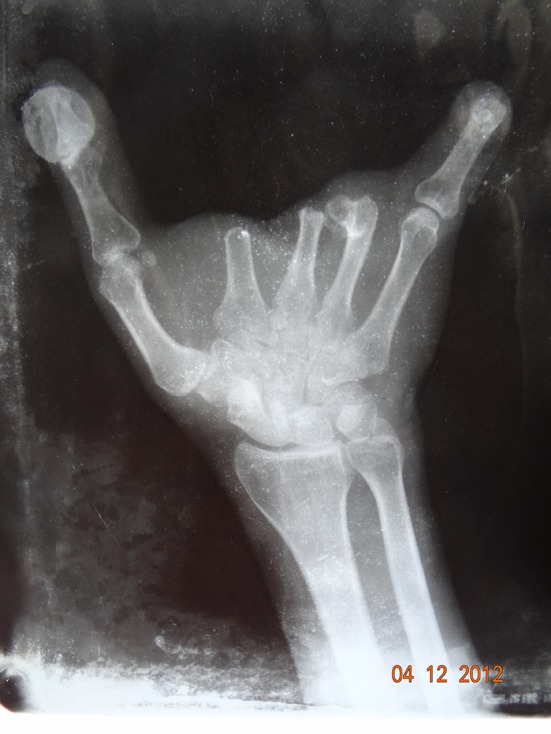

Fig. 2.

Radiograph of the patient’s hand

A 52 year old male patient reported to the Department of Prosthodontics, Tamil Nadu Government Dental College and Hospital, Chennai, India with a chief complaint of missing lower anterior teeth. He had a history of trauma to his left hand while working in factory one year back. On examination there was gross, soft tissue and hard tissue defect with missing left index, middle and ring finger also, some soft tissue defect of little finger was also seen (Fig. 1). On radiographic examination, there was loss of left index, middle and ring finger at the level of distal heads of respective meta-carpals (Fig. 2). The distal phalanx of the little finger was also missing. The amputated area showed normal surrounding area and no signs of any infection or inflammation.